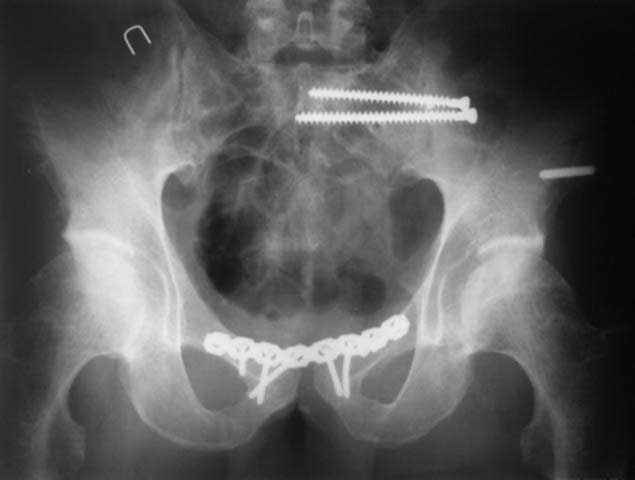

закрытое низведение правой половины таза кольцевым аппаратом (с фиксацией задних отделов), затем проведение илиосакральных винтов, реостеосинтез лонного сочленнения, дальнейшая фиксация в аппрате 2-3 мес. Похожий пример в приложении.